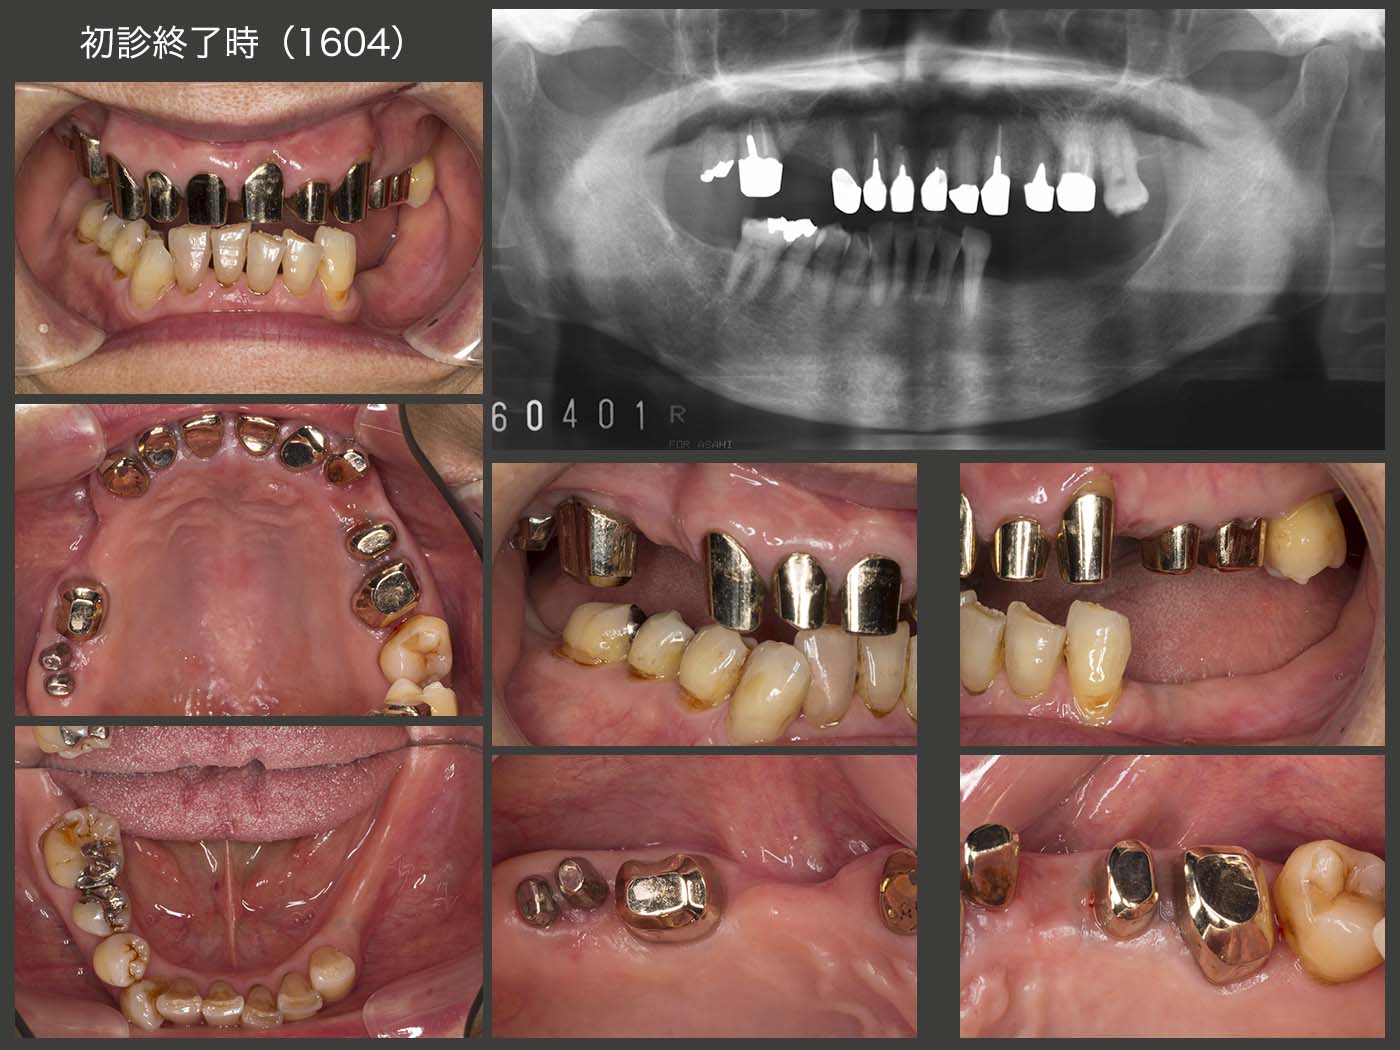

2014年4月初診,76歳女性.主訴は右上6の違和感.臼歯部で咬合しているのは右側の上下6のみであり,当然ここが咀嚼の中心となり,力学的にそこに問題が生じやすい.

まず,右下5および6のう蝕処置を行った後に下顎に暫間義歯を装着し,下顎位を確保すると同時に,食感は味わいにくいが左側でも嚙める状態にした.この際,左下4および5の残根は咬合力が加わると痛みが生じたため抜去した.つぎに,左上3の感染根管治療および全体の歯周基本治療を行った.主訴の右上6は近心舌側に10mmの歯周ポケットがあった.とりあえず,1ヵ月間感染根管治療を施したが,歯周ポケットが全く改善しなかったため,抜去した.

2014年10月に右上6を抜去し,15年2月に右下7を右上6部に移植した.この際,ドナー歯に挻出力を与え抜歯しやすいように工夫し,また受容側においては,メスで顎堤中央部に切開を加え,頰側の歯槽骨を側方に押し広げた.

2015年6月,ほぼ全ての基礎治療が終了した状態.移植歯も特に問題なく機能している.上顎は条件の悪い歯が多いため,将来の変化に対応しやすいコーヌス義歯を選択することにした.下顎は,暫間義歯で特に問題がなかったため,この形を踏襲し,大連結装置に強度を保たせた金属床義歯を製作することにした.

2016年4月,初診終了時の状態.移植歯の歯周ポケットは頰側で5mm認められた.水平的動揺も若干あり,将来が心配な状況であった.左上6の遠心は初診時8mm,初診終了時にも6mm残存してしまった.もちろん,歯根端切除術を施した左右1の予後も心配である.このように,上顎に予後不安な歯が多いが,可撤式義歯なので将来何とか対応できるのではないかという安心感もある.下顎は全ての残存歯が有髄歯なので将来の不安は少ない.